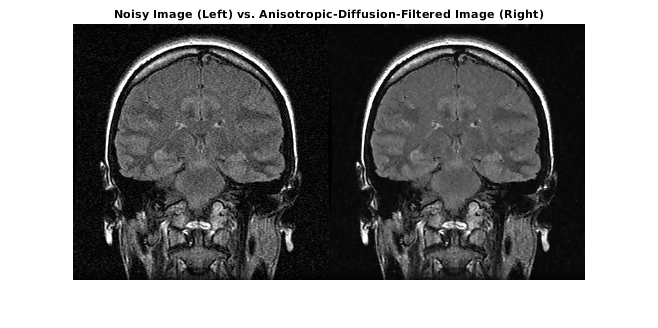

Загрузите шумный 3-D полутоновый объем MRI.

load mristackВыполните осведомленное о ребре шумоподавление на объеме с помощью анизотропной диффузии. Чтобы предотвратить сверхсглаживание низкоконтрастных функций в мозгу, сократите число итераций от номера по умолчанию, 5. Компромисс - то, что меньше шума удалено.

diffusedImage = imdiffusefilt(mristack,'NumberOfIterations',3);Чтобы сравнить шумное изображение и отфильтрованное изображение подробно, отобразите десятый срез обоих.

imshowpair(mristack(:,:,10),diffusedImage(:,:,10),'montage') title('Noisy Image (Left) vs. Anisotropic-Diffusion-Filtered Image (Right)')

Вычислите счет Средства анализа качества изображения естественности (NIQE), усредненный по всем срезам в объеме. Счет NIQE обеспечивает количественные показатели качества изображения, которое не требует ссылочного изображения. Понизьтесь баллы NIQE отражают лучшее перцепционное качество изображения.

The NIQE score of the noisy volume is 5.7794.

The NIQE score using anisotropic diffusion is 4.1391.

Счет NIQE сопоставим с наблюдением за уменьшаемым шумом в отфильтрованном изображении.